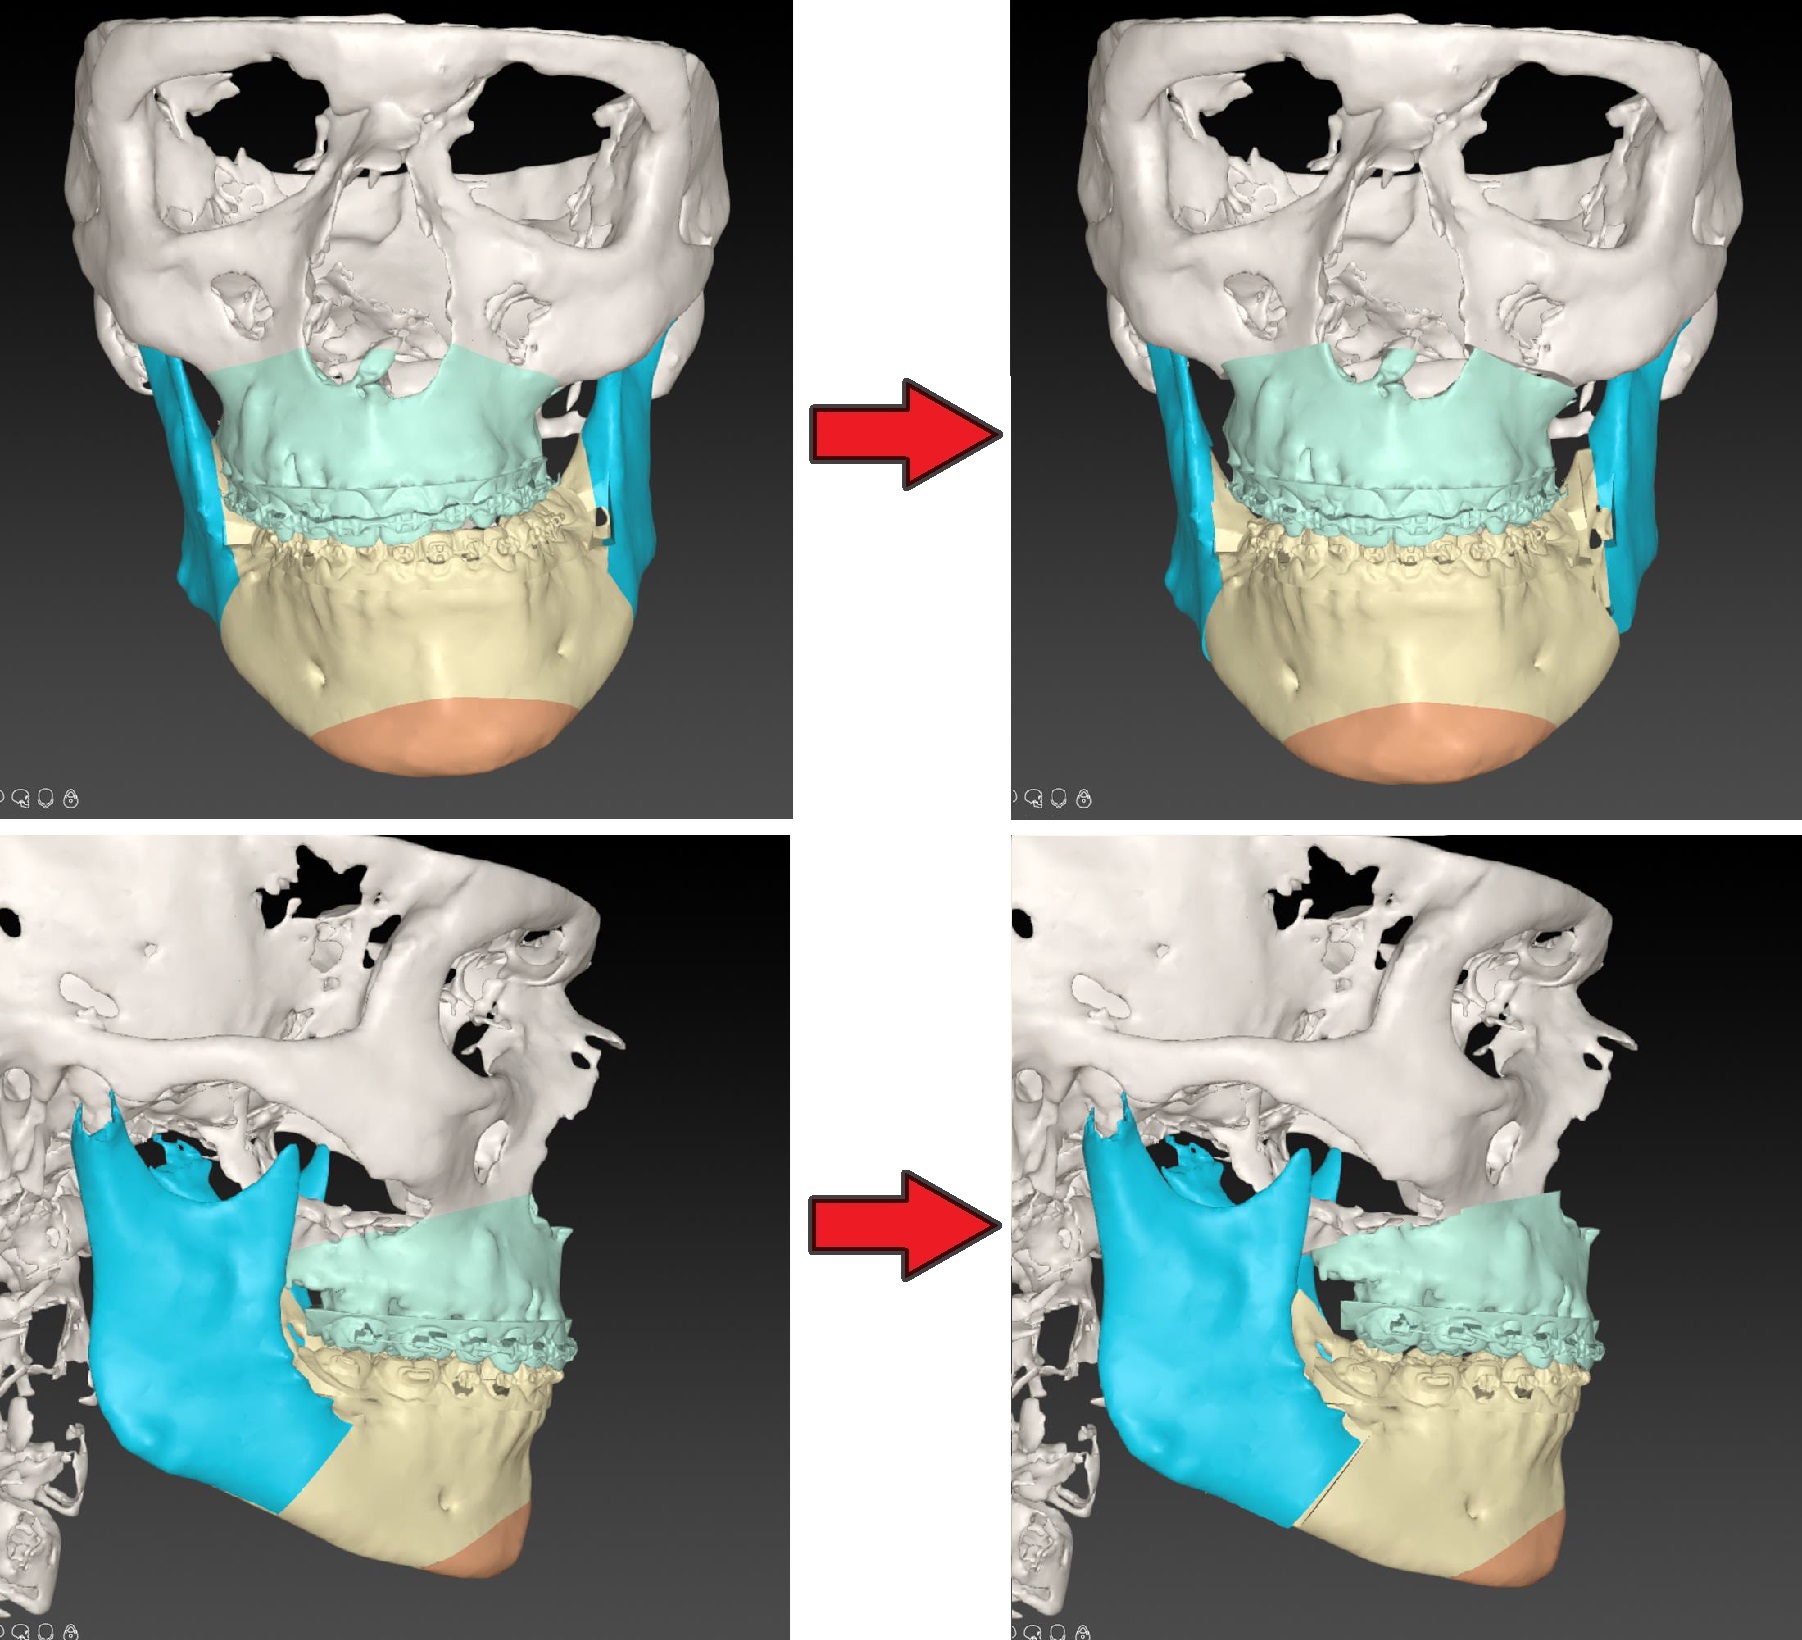

Digitale 3D-planning van de operatie

Orthodontie door Ortho Leiden

Operatie door W. van Hout, LUMC